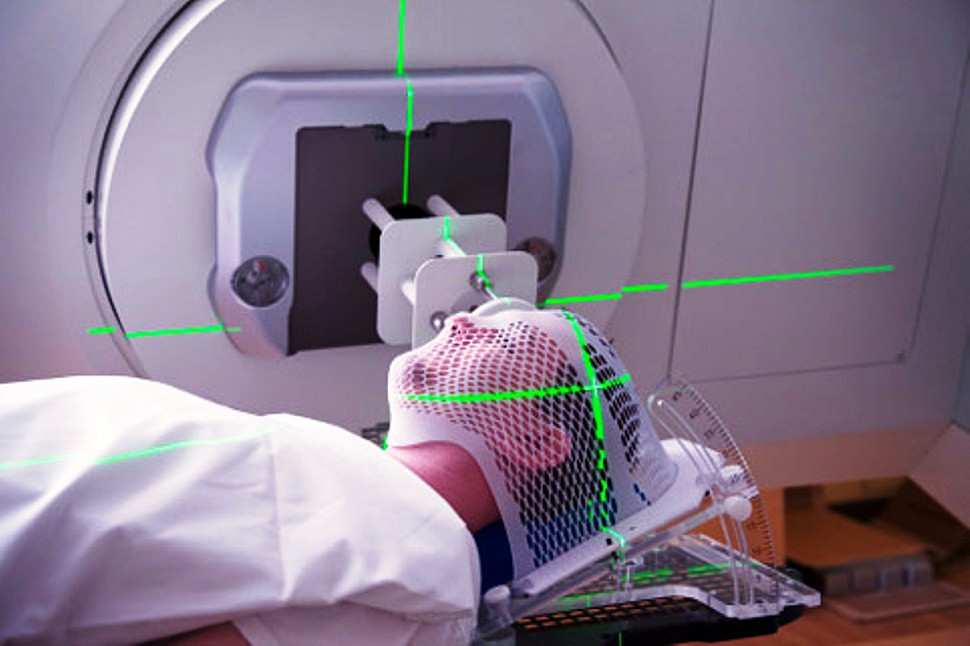

Радиотерапия — лечение проводится, когда новообразование нельзя удалить скальпелем. На опухоль прицельно направляются гамма-лучи, что позволяет уменьшить плохое воздействие на здоровые ткани. Пациент проходит терапию в специальной маске из плексигласа, которая четко фиксирует голову и помогает добиться точной направленности лучей. Противопоказаний для этого метода нет.